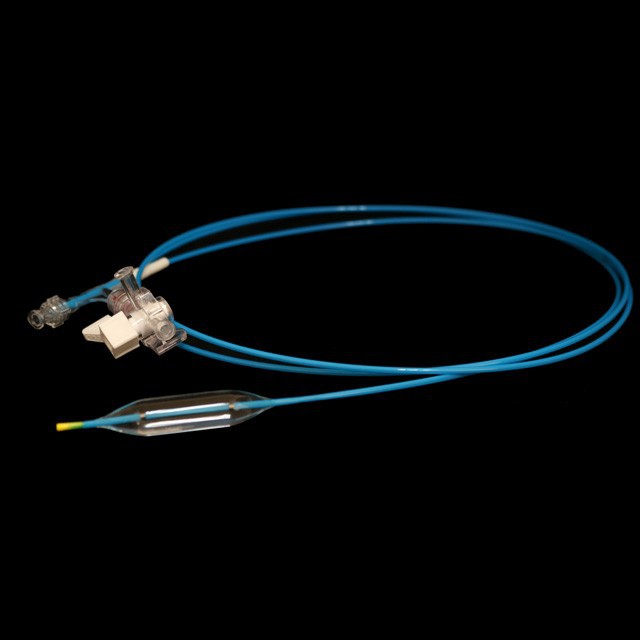

● Elastic yakapfava tip dhizaini, iyo inogona kupinda mukati medu pachinzvimbo chakanangana nechinzvimbo chisina kukuvara {}

● Kukurumidza kudhirowa dhizaini kunobatsira kuderedza kuvhiyiwa nguva .

● Shandisa zvinhu kunze kwenyika zvine simba rekumanikidza kudzvinyirira uye yakachengeteka dhalation .

● Sangano rekugadzira mushure mekutya-mapapiro-mapapiro emapapiro kunopa kukurudzira kwakanakisa uye kuchinjika kudzoka kubva pakushanda chiteshi {{1}

● Kugadzira kurongeka kwehubhu kunoita kuti zvive zvatakapfidza uye nezvakanaka zvakanaka, zvinokatyamadza kupokana nekukasira uye kupfuudza nyore nyore .

● Iyo adigaque mamaki pamigumo miviri yeballoon inogona kupa chaiyo chinzvimbo pasi pe x-ray .

● Pre-input 0 . 035 "kutungamira waya neye nyoro nyoro uye mucherechedzo, iri nyore kufungidzira urefu hwemukati wemukati waya.